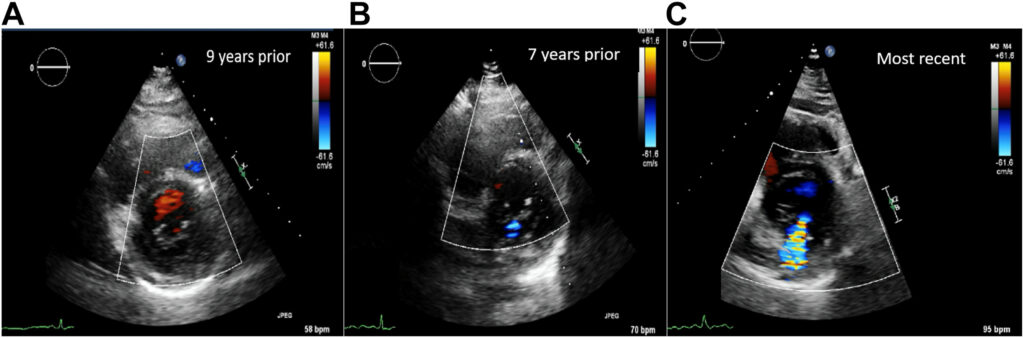

Ecocardiograma bidimensional demonstrou ventrículo esquerdo com diâmetro normal, fração de ejeção (FE) preservada (60-65% pela análise subjetiva) e uma insuficiência mitral (IMi) moderada (EROA 0.26 cm², volume regurgitante 38 ml, fração regurgitante 42%).

A VMi tinha aparência trivalvular, com o folheto posterior apresentando uma divisão assimétrica. Dois músculos papilares foram observados.

Após discussão com equipe médica, foi optado por tratamento clínico. Um exame prévio, realizado 09 anos antes, mostrou que houve progressão da IMi.

Ecocardiograma de 09 anos antes demonstrava apenas uma IMi discreta. O paciente foi submetido a estudo transesofágico cujo resultado mostrou uma VMi trivalvular com IMi importante originada de um folheto posterior dividido de forma assimétrica.